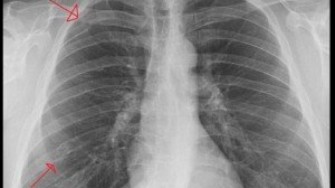

La survenue d´une fracture de cote chez un homme âgé doit faire rechercher une ostéoporose. Telle est la conclusion d´une étude prospective multicentrique américaine (The Osteoporotic Fractures in Men ou MrOS Study) menée sur près de 6 000 hommes âgés de 65 ans et plus. Les participants ont été interrogés par courrier tous les quatre mois pendant 6 ans sur le nombre de chutes et/ou la survenue de fractures (validées par des radiographies). Durant le suivi, un quart des fractures non vertébrales rapportées par les participants étaient de fractures de cote, soit une incidence de 3,5 pour mille patient-année. Un âge > 80 ans, une densité minérale osseuse basse, des difficultés dans les activités quotidiennes instrumentales et un antécédent de fracture de cote ou du thorax étaient des facteurs indépendants de risque de fracture de cote. Un antécédent de fracture de cote ou thoracique multipliait par plus de deux le risque de faire une nouvelle fracture de cote (HR 2,71%, IC 95% :1,86-3,95), de hanche (HR 2,05, IC95% :1,33-3,15) et du poignet (HR 2,06, IC95% :1,14-3,70). L´incidence cumulative des fractures de cote chez les hommes ayant un antécédent de fracture de cote était beaucoup plus élevée que celle des hommes sans fractures de cote dans leur passé. L´ensemble de ces données incitent à penser que les fractures de cotes chez les hommes âgés sont d´authentiques fractures ostéoporotiques et doivent être traitées comme telles.